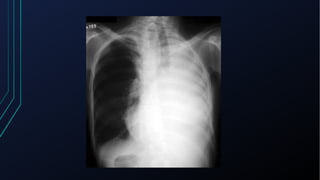

• Pode estar deslocada em processos tumorais do pescoço e

mediastino e em doenças pulmonares (pneumotórax, derrames

pleurais, atelectasias)